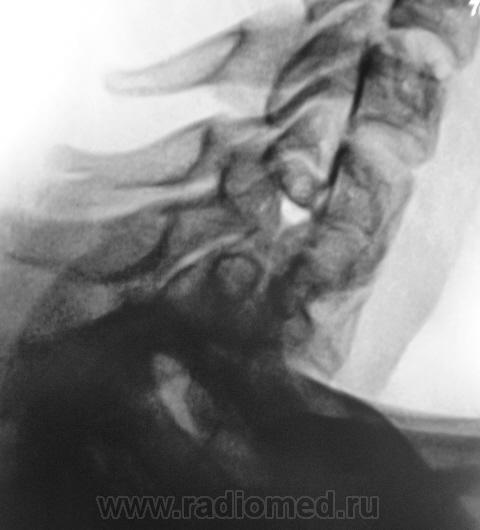

Подросток направлен в рентгеновский кабинет с диагнозом "сколиоз"...

Сколиоз-то сколиоз, но генеза "аномального".

Это синостоз тел верхних шейных позвонков и С6-С7? И боковые клиновидные полупозвонки в верхнегрудном отделе? Это синдром Клиппеля-Файля? А может и Шпренгеля...